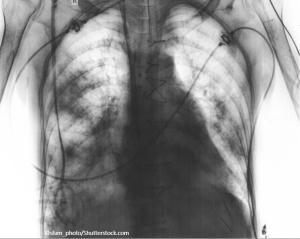

Two weeks after injury to the right chest wall and shoulder, the patient continues to have pain. He also reports numbness and tingling in his hands bilaterally. What do the ED images reveal?